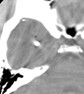

A case series from Amirjamshidi et al14 reported long-term follow-up data on 99 patients of 191 victims of the Iran-Iraq conflict who were treated at two centers affiliated with Tehran University of Medical Sciences.15 These patients ranged in age from 13 to 55 years and all were male. Patients received no initial surgical interventions for pTBIs obtained in battlefield areas due to shrapnel and shell fragments. Patients who had a GCS score of 8 or higher, no rapid deterioration in consciousness, and a small entrance wound of less than 2 to 3 cm were candidates for local treatment. Patients were treated with wound cleaning, local debridement, stitches, and dressing at a field hospital. They were then transferred to a medical center where better X-rays and computed tomography (CT) scans were taken and cases were reviewed by the attending surgeon. Sixty-two cases had CSF leakage, or the wound was under tension, requiring more superficial debridement of the skin, bone, and any contused brain tissue; however, the attending surgeon determined more extensive debridement was not necessary. Patients were then admitted, treated with antibiotics for 2 weeks, and had at least two additional CT scans. Mean follow-up was almost 8 years, in which time 91% of patients had good outcomes and were able to perform their usual job/activities, 4% were severely disabled, and 5% had died of their injuries or meningitis. None of the patients had brain abscesses, epilepsy, or hematomas. Outcomes were not significantly different for the 37 patients who did not require additional superficial debridement after transfer compared with the 62 patients who did.

In a another series reported by Taha et al6, 32 patients from conflict zones in Lebanon with shrapnel (84%) or gunshot injuries (16%) were treated within a mean of 3 hours after injury6, in an emergency room, with superficial entry wound debridement and wound closure without drainage. Patients had to have a GCS greater than 10, an exam within 6 hours of the injury, a small entry wound, no exit wound, and to meet other criteria related to missile tract and hematomas (Table). Patients ranged in age from 3 to 51 years with a mean age of 32 years. Most (19 of 32) patients had an initial GCS of 15. At follow-up (mean 3.5 years after injury) there were no deaths and no neurological deficits. Only one patient (3.1%) had complications including a seizure and then a brain abscess that was excised; however, 2 months later the patient had no abnormalities.